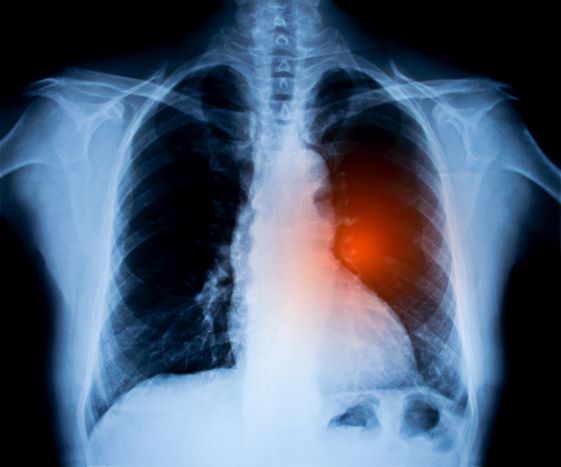

DÜSSELDORF 03/02 Indien bij de tumorstadiëring onduidelijke focale bevindingen worden ontdekt, moet niet alleen worden gedacht aan metastasen van de primaire tumor, maar ook aan andere tumorentiteiten. Gynaecologen van het Universitair Ziekenhuis Düsseldorf adviseren om, indien mogelijk, een histologisch onderzoek uit te voeren om de diagnose te bevestigen. De aanleiding daartoe is de ziektegeschiedenis van een jonge borstkankerpatiënte.